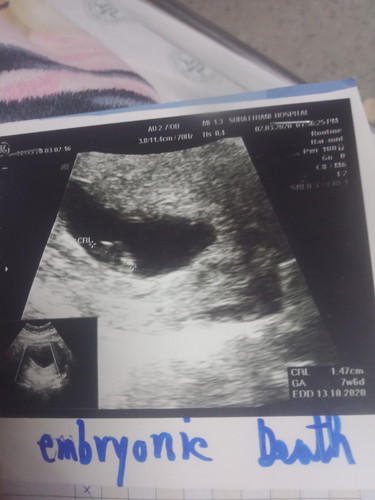

ตอนนี้น้องได้เสียแล้วคะน้องหัวใจไม่เต้นหมอได้ยุติการตั้งครรถ์